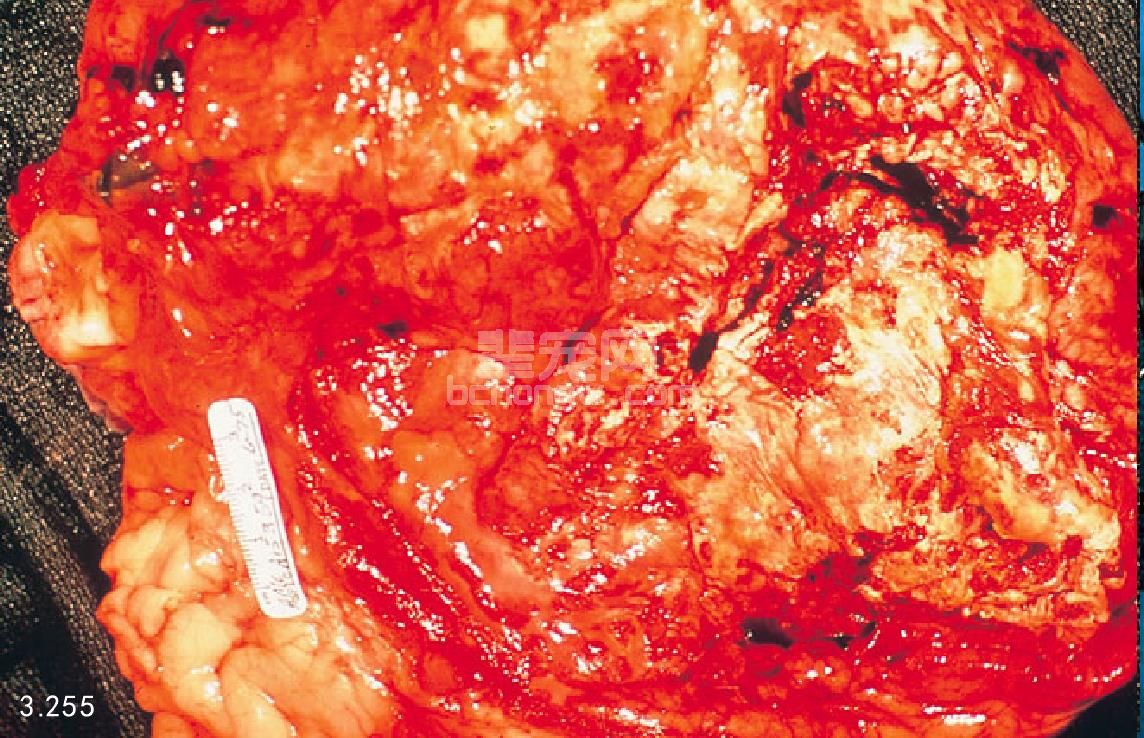

图3.255 图3.252中的患犬还有广泛的胰腺蜂窝织炎形成,这只犬胰腺炎的发病机制是甲状腺功能减退引起明显的高血脂,反过来高血脂又诱发急性胰腺炎。已知高血脂是引起人急性胰腺炎的常见原因。